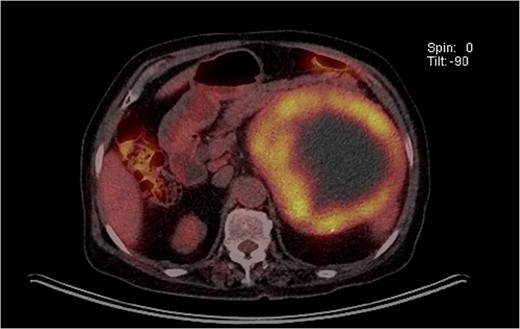

An 87-year-old female, with no past medical history, was admitted to the emergency center in our tertiary institution with a 1-month history of abdominal pain and discomfort. Initial workup using abdomino-pelvic computed tomography (APCT) presented a 16-cm-sized heterogeneous tumor in the left adrenal gland (Fig. 1). She was referred to the endocrine department for further evaluation. The results of laboratory tests, including those for measuring plasma levels of adrenocorticotrophic hormone, cortisol, aldosterone, epinephrine, norepinephrine, metanephrine, dehydroepiandrosterone sulfate as well as urine levels of epinephrine, norepinephrine, metanephrine, vanillylmandelic acid and homovanillic acid were within normal limits. Plasma renin activity was also normal. The levels of serum markers for carcinoma were within normal limits radiolabeled metaiodobenzylguanidine single photon emission computed tomography (I-123 MIBG SPECT) presented a huge mass with mild peripheral uptake of the left adrenal gland (Fig. 2). Finally, positron emission tomography (PET) was done for evaluation of distant metastasis. PET showed the accumulation of fluorodeoxyglucose (FDG) in the left adrenal tumor with [maximum standardized uptake value (SUVmax: 7.4)] and lymph nodes in the para-aortic area (SUVmax: 2.4; Fig. 3). We initially expected adrenocortical carcinoma with lymph nodes metastasis.

PET showed the accumulation of FDG in the left adrenal tumor and lymph nodes in the para-aortic area.